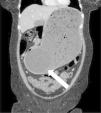

A 45-year-old woman came to the emergency service due to 3 days of ongoing vomiting and significant generalized and progressive abdominal distension. Her past medical history was unremarkable, except for the placing of an intragastric balloon 3 weeks prior. Plain abdominal x-ray revealed an occupied abdomen and bowel loop displacement toward the periphery. A computed axial tomography scan identified severe dilation of the gastric corpus, along with the intragastric balloon (white arrow), which was embedded in the antral region, causing the gastric outlet obstruction (Figure 1 in the axial plane, Figure 2 in the sagittal plane, and Figure 3 in the coronal plane). According to the medical literature, frequency of overall complications from intragastric balloon placement reaches 2.6% and obstruction is one of the most common causes in the early postoperative period, with a frequency of 0.8%. First, a nasogastric tube was placed in our patient to relieve the distension, after which the obstruction was resolved through endoscopic removal of the balloon. After the intervention, the suggested cause was the progression of the balloon and its lodging in the antrum of the stomach, with no excessive filling of that gastric region.